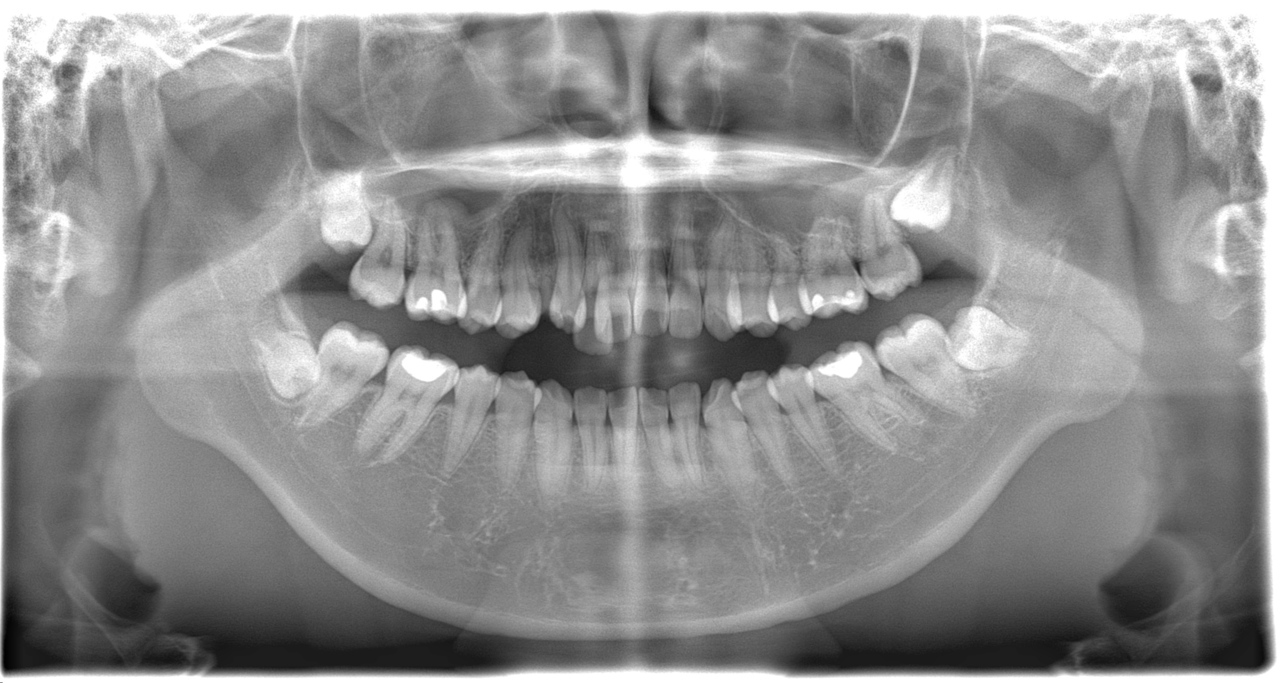

歯ならびの改善を主訴に来院されました。上顎右側に乳歯

(子供の歯)が残存している状態でした。また、下の歯に叢生がありました。患者さんとカウンセリングを行い、マルチブラケット装置によるワイヤー矯正治療を行いました。

はじめに、乳歯の抜歯を行い、乳歯を抜歯したスペースに永久歯を配列しました。また、舌側に位置していた永久歯も上顎の歯列に配列しました。全体の歯の配列が整ってきたので、顎間ゴムにて咬合の緊密化を行い、矯正治療を終了しました